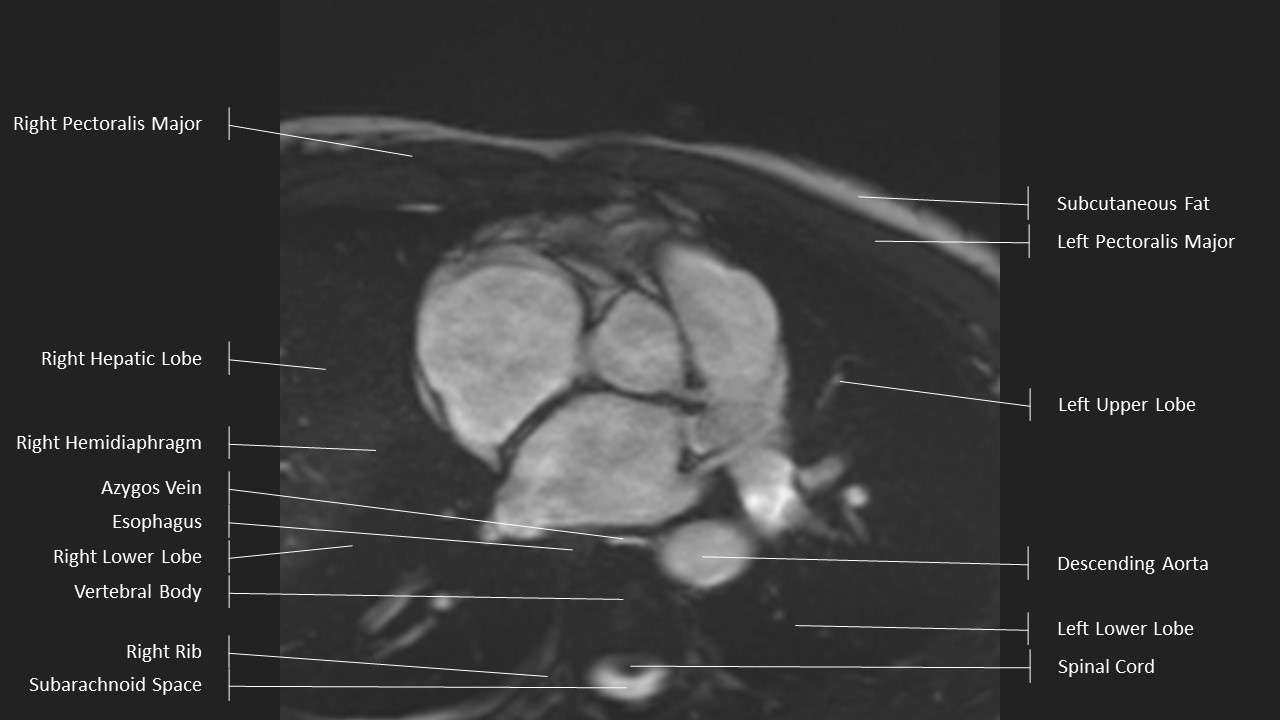

Axial Series